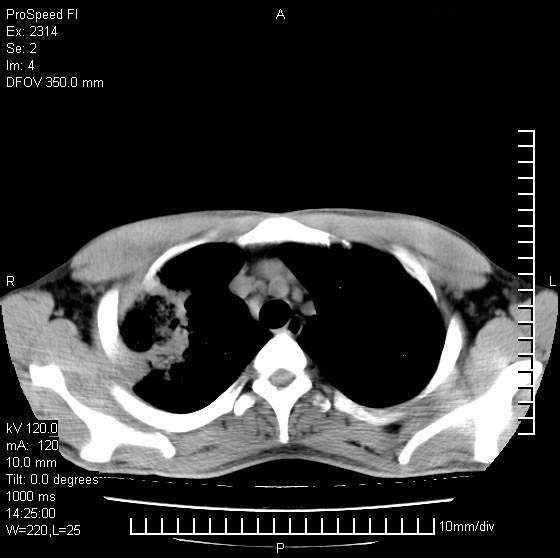

男性,再生障碍性贫血,入院前发热10天,最高40c,右侧胸痛,外院ct示右上,中肺边缘模糊的球性影(就是我现在图中标示的范围),考虑炎症,在我院使用头孢呋辛,洛美沙星10天,高烧消退,自感下午稍有发热,但今天ct示右上,中肺病灶明显扩大,还是考虑炎症,看其中的球型影是否霉菌感染??,是否能排除结核?

右肺中叶外侧段病变,上缘界限不清,下缘锐利,以段性发病为主,内见巨大空洞及空洞内容物,结合病史首先考虑:化脓性肺炎。不除外霉菌感染!

片状高密度影内见空洞影,内可见球形软组织密度影,并有新月征,考虑霉菌感染.